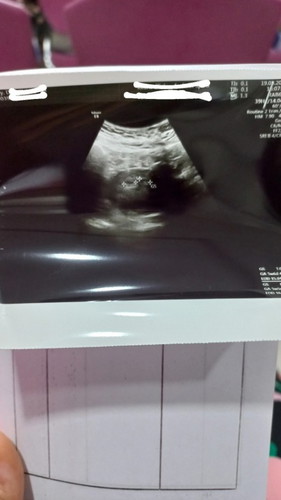

Bun share pengalaman nya dong, ada gak pas USG 5w6d dokter bilang ada 2 kantung kehamilan.??

Sya dan suami tidak ada riwayat kembar..

ditunggu aja Bun.....smoga aja twins n sehat semua..,

belum keliatan bun